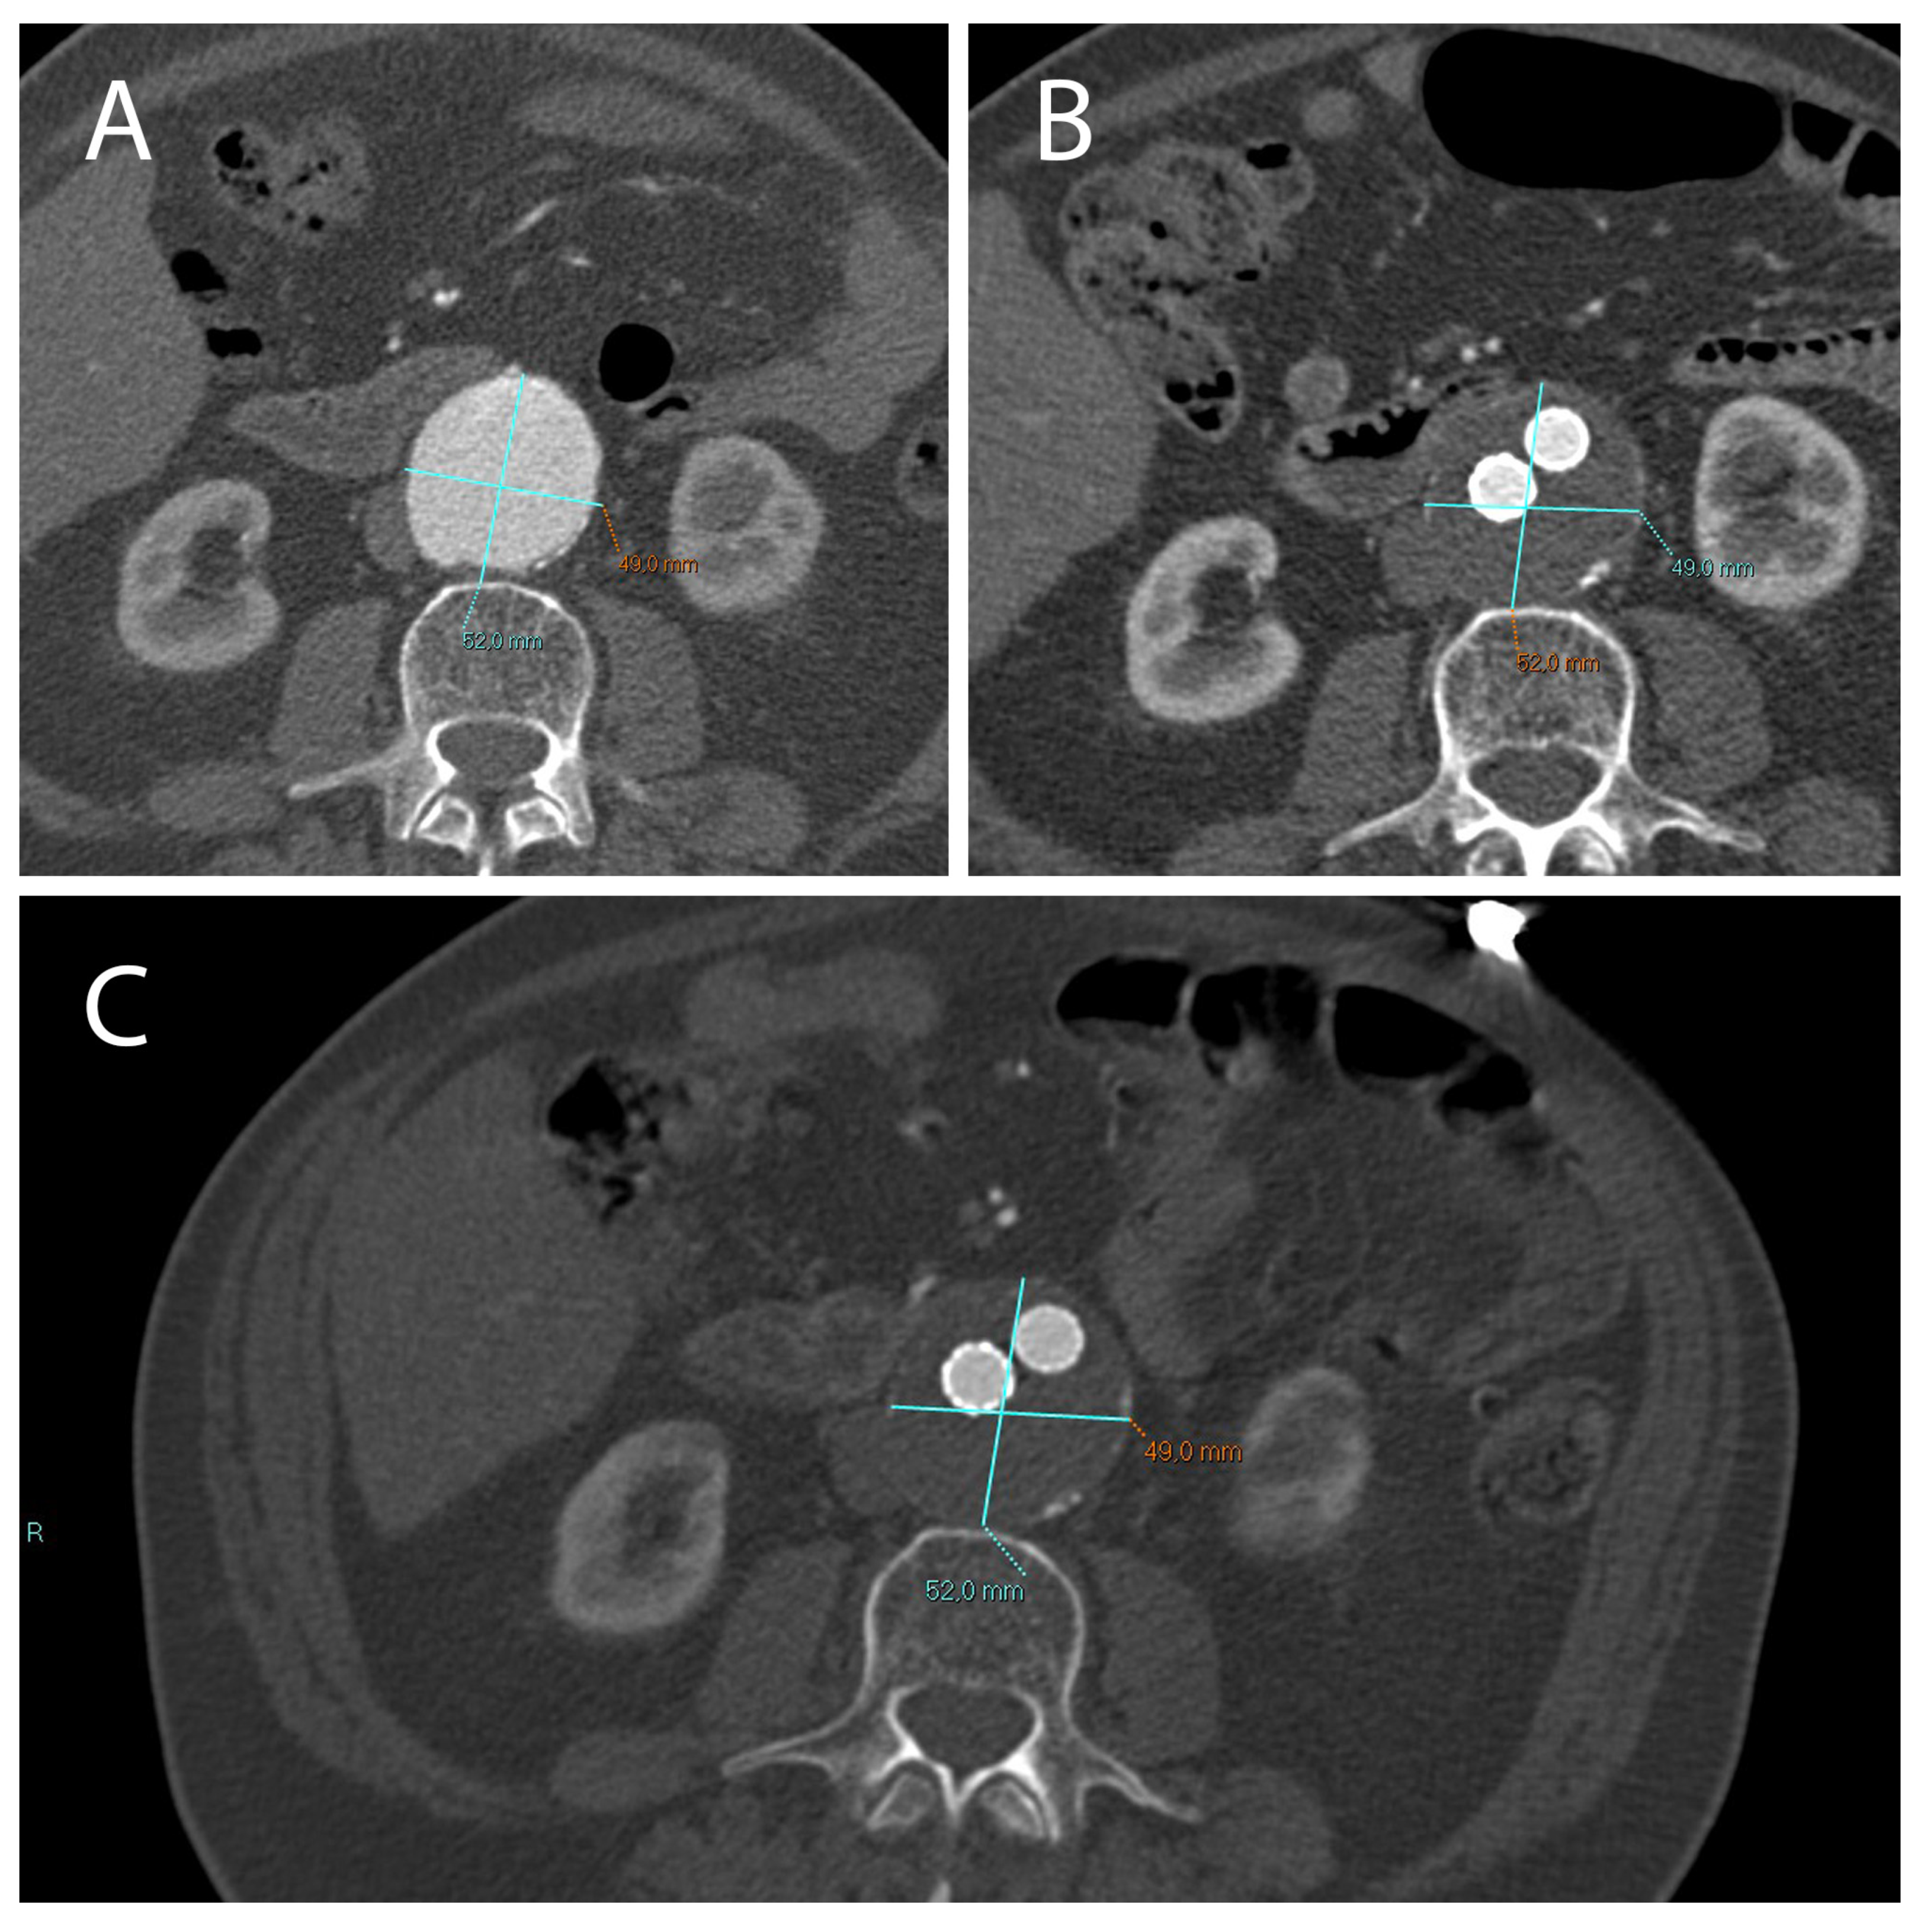

Figure 1. (A) CTA axial images show an AAA with a diameter >5.5 cm (in this case 5.8 cm) which can be treated with EVAR. (B) After 1 month following EVAR implantation, CTA was used to assess endoleak occurrence; of note, there was no significant reduction in AAA diameter in this short time-range. (C) After 12 months following EVAR intervention, a correct aneurysmatic sac exclusion without endoleak led to a significant reduction in AAA diameter (in this case the aneurysm diameter went from 5.8 cm to 4 cm).

Figure 3. A not correctly excluded AAA treated with EVAR, with the presence of an endoleak. Treatment did not result in a reduction in aneurysm diameter compared to the pre-EVAR CTA (A). CT images obtained 1 month (B) and 12 months (C) after EVAR implantation.

The analysis of clinical data confirmed, that in the cohort of patients not displaying endoleaks a significant decrease in AAA size occurred between 1 and 12 months after EVAR implantation (mean decrease ~0.98 cm; p < 0.0001) (Figure 1 and Figure 2B). In patients with endoleak presence and persistence on the other hand, no statistical AAA size variations were registered during the same time range (Figure 2A and Figure 3).